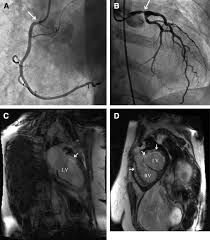

Radiation induced CAD may manifest as resting or inducible regional wall motion abnormalities in typical coronary distributions. Patient developed radiopneumonia and symptoms of acute pericarditis in 1967.

2 The coronary ostia are typically affected. RIHD comprises a spectrum of heart disease including cardiomyopathy pericarditis coronary artery disease valvular heart disease and conduction system abnormalities. There is a latent interval of 1020 years between radiation exposure and development of clinically significant heart valve disease. Radiation-induced heart disease can manifest as pathology of the epicardial and endocardial coronary vessels resulting in coronary obstruction semilunar and atrioventricular valves resulting in stenosis or regurgitation due to valvular fibrosis myocardium with resultant cardiomyopathy and conduction system and pericardium with pericardial constriction and inflammation. Although valvular disease is common in patients with RIHD clinically signifi cant dis-ease is not. There are abnormalities numerous clinical manifestations of RIHD such as chest pain palpitation and dyspnea even without obvious symptoms. Women and the elderly are more likely to present with atypical features.